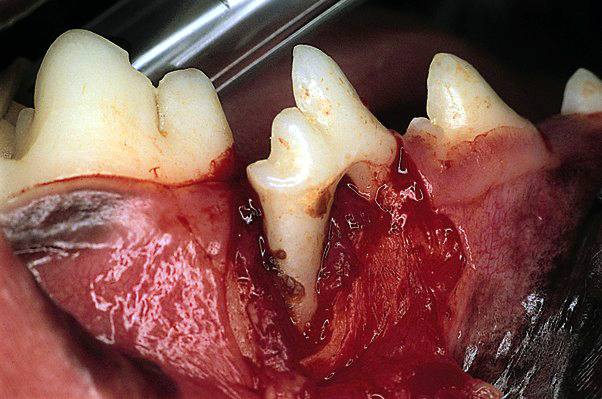

Grossly severe disease

Attachment loss is now greater than 50%. If disease is generalised, horizontal bone loss is most likely, whereas localised lesions, such as the palatal aspect of the maxillary canines, may present infrabony pockets with vertical bone loss.

Severe/total attachment loss of mesial root 408